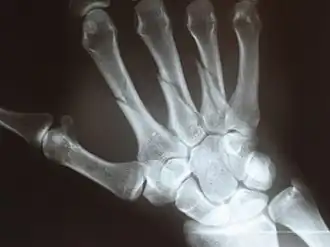

![]() Перелом пястных костей | |

Пястные кости (лат. ossa metacarpi) — пять коротких трубчатых костей кисти, лучами отходящих от запястья. Нумерация пястных костей соответствует нумерации сочленяющихся с ними пальцев. В пястных костях различают основание (лат. basis), тело (лат. corpus) и головку (лат. caput).

Утолщенный проксимальный конец пястной кости называется её основанием. Пястная кость сочленена как с дистальным рядом костей запястья, так и с соседними пястными костями. Тело пястной кости (её основная часть) имеет несколько изогнутую к тылу форму, содержит питательный канал (лат. canalis nutricius), открывающийся с ладонной стороны кости питательным отверстием (лат. foramen nutricium). Головка (дистальный эпифиз) пястной кости шаровидная, её суставная поверхность несколько возвышена с ладонной стороны.